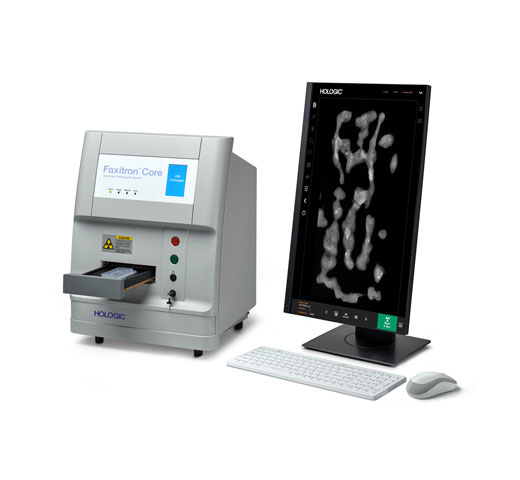

Breast Health

Hologic is transforming breast care. We apply cutting-edge science to accelerate discovery, improve efficiency and continually sharpen precision.

Time is precious when it comes to effective detection, diagnosis and treatment of breast cancer. We strive to save you time at every step along the Continuum of Care.

Browse Products